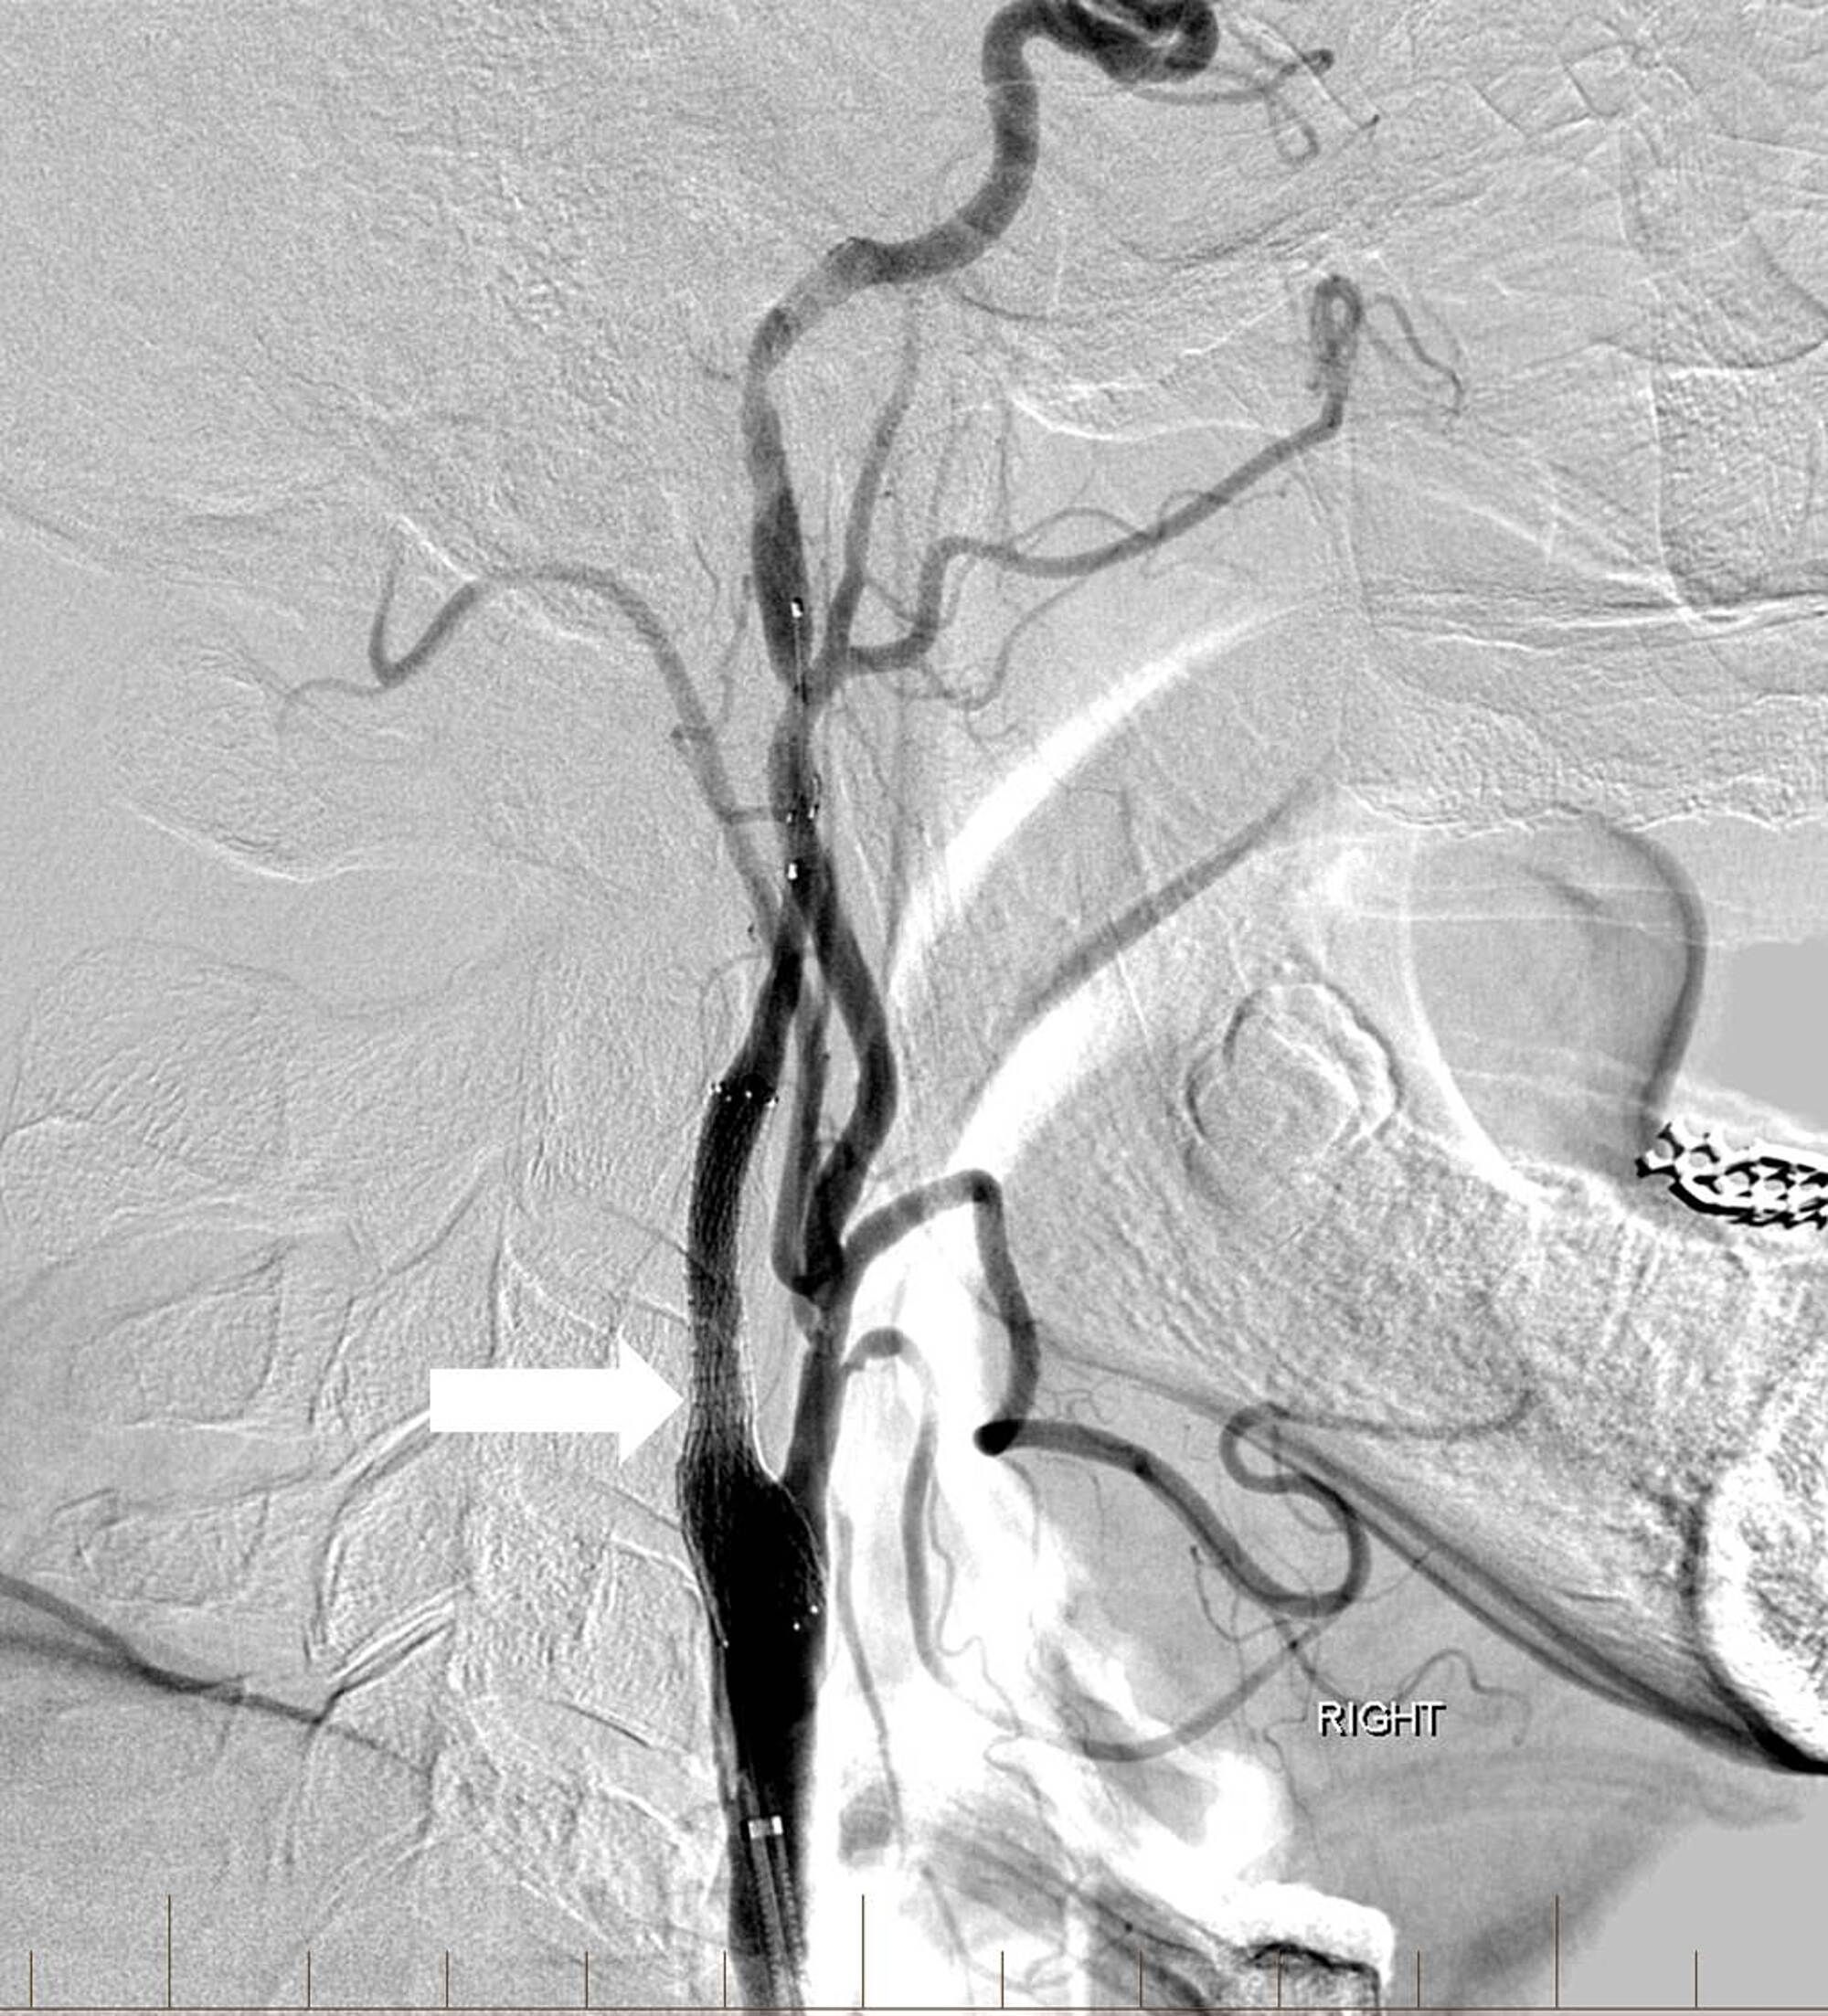

A 63-year-old man with a history of hypertension, hyperlipidemia, peripheral artery disease, smoking, and Stage IV lung cancer presented with left-sided weakness and dysarthria when he visited our institution for a chemotherapy port placement. His National Institutes of Health Stroke Scale (NIHSS) score was six and he was not a candidate for intravenous (IV) thrombolytics. Computed tomography angiography (CTA) revealed occlusion of the extracranial right internal carotid artery (ICA) and right middle cerebral artery (MCA) but no hemorrhage or large areas of acute ischemic change. Biplane digital subtraction angiography (DSA) revealed tapering to occlusion of the proximal right cervical ICA at the level of the carotid artery bulb (Figure 1).